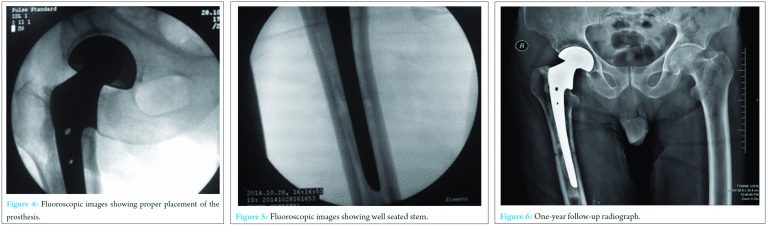

We applied the Schanz pins just proximal to the amputation stump as they will not obstruct the stem of the prosthesis. The first Schanz pin was applied from the lateral aspect with the limb in neutral position and perpendicular to the bone under c-arm guidance. The second Schanz pin was applied in the anteroposterior plane perpendicular to the first Schanz pin. The hip was approached by the standard lateral approach. After exposing the fracture site, neck cut was performed and head delivered. The canal was rasped and in view of a wider canal cementing was done and bipolar prosthesis inserted. There was no restriction of the length of the prosthesis as the length of the amputation stump was adequate. The prosthesis was inserted 10° anterior to the sagittal Schanz pin to maintain the version. Traction and internal rotation was applied using the Schanz pins and the joint relocated. Position was verified on fluoroscopy (Fig. 4 and 5) and intraoperative stability confirmed. The Schanz pins were removed. The wound was closed in layers over a vacuum suction drain and a separate dressing was done for the surgical site and amputation stump.

During the immediate post-operative period, the patient was clinically stable without any complication. Physiotherapy with isometric exercises was started after 48 h, and the patient was mobilized with the help of walker after 4 days. The patient was discharged on 7th post-operative day and was again reviewed 10 days later for suture removal. The patient began to walk full weight bearing walking with above-knee prosthesis with walker support at 6 weeks. He began to walk without any support with above-knee prosthesis at 10 weeks. Now at 14 months, the patient is comfortable, pain-free and walking full weight bearing without any support (Fig. 6).